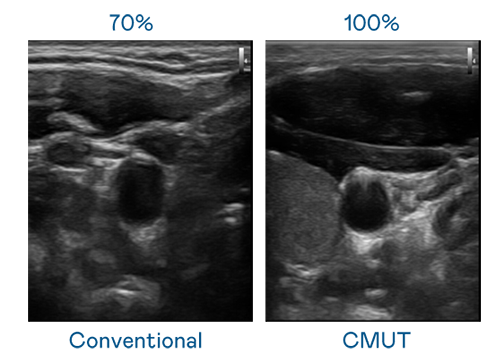

CMUT 技术是一种用电容式微机电元件来产生超音波讯号的技术。与传统 PZT 压电式技术相比,CMUT 频宽增加 30%,更宽频的超音波讯号让影像解析度大幅提升,是实现高影像品质医疗超音波扫描、促进精准医疗发展的关键技术。

大频宽带来超清晰影像

超音波影像的解析度高低,首先取决于探头能发出的讯号频宽。j9九游会登录入口首页j988me CMUT 可提供高清晰的超音波讯号,提供高频宽、高灵敏度、影像纹理细节更高的超音波影像,协助医护人员缩短影像判读时间及利用精准的医疗影像进行诊断。